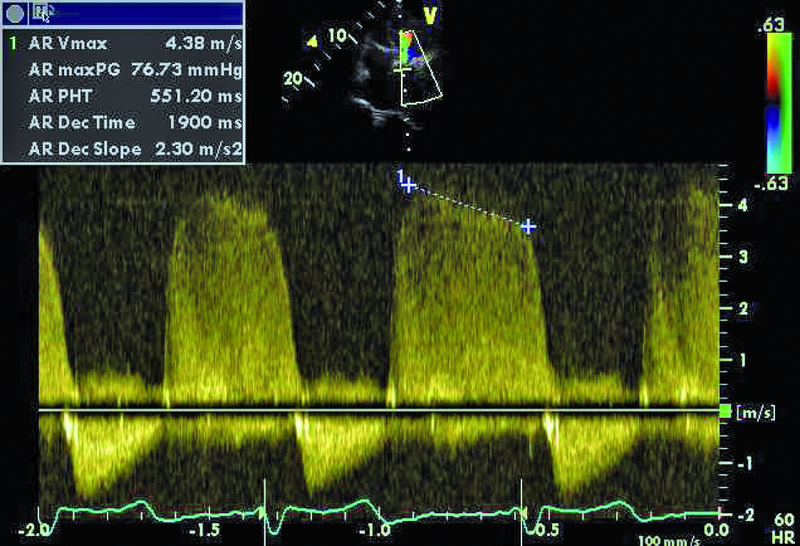

Kobieta, lat 80. Jakie patologie można rozpoznać na rycinach?

5. Niedomykalność zastawki aortalnej (ryc. 4).